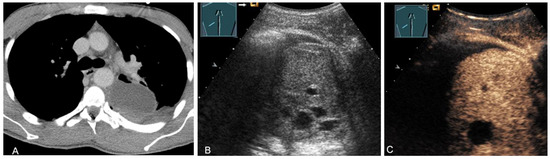

2.5. Solid and Cystic Primary Tumors

The spectrum of primary mediastinal masses includes a heterogeneous group of benign and malignant pathologies [28,31,36]. Benign primary mediastinal masses include congenital cysts (Figure 14), lipomas, thyroid tissue (Figure 15), benign thymomas, thymic residues, scar tissue, ganglioneuromas (Figure 16), schwannomas (Figure 17), and giant cell tumors (Figure 18) [28,31,36].

Figure 14.

A cystic mediastinal mass on CT (provided by Prof. Dr. Andreas H. Mahnken, Marburg, Germany) (A), B-mode US (B), and CEUS (C), surgically confirmed as a mediastinally located bronchogenic cyst.

Figure 15.

An echogenic mediastinal mass as an incidental finding on CT (provided by Prof. Dr. Andreas H. Mahnken, Marburg, Germany) (A), B-mode US (B), and CEUS (C), evaluated by imaging as a retrosternal located thyroid gland.

Figure 16.

A young patient with tumor formation in the paravertebral mediastinum on CT (provided by Prof. Dr. Andreas H. Mahnken, Marburg, Germany) (A), B-mode US (B), and CEUS (C), surgically confirmed as ganglioneuroma.

Figure 17.

A young patient with tumor formation in the paravertebral mediastinum on CT (provided by Prof. Dr. Andreas H. Mahnken, Marburg, Germany) (A), B-mode US (B), and CEUS (C), surgically confirmed as schwannoma.